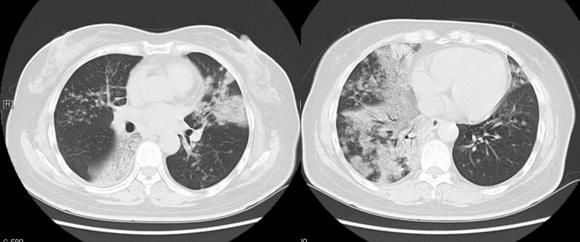

下图是一位52岁的女士,咳嗽低热一个月,伴有较多白色泡沫样痰,CT发现双肺多发斑片状及磨玻璃结节状影,边界不清,内可见支气管充气征,后来确诊为粘液腺癌,癌细胞随着黏液,沿着气道四处播散,已经没有手术机会了:

好在这位女士对化疗敏感,而且很幸运地基因检测阳性,通过化疗和靶向治疗,生存了5年多。